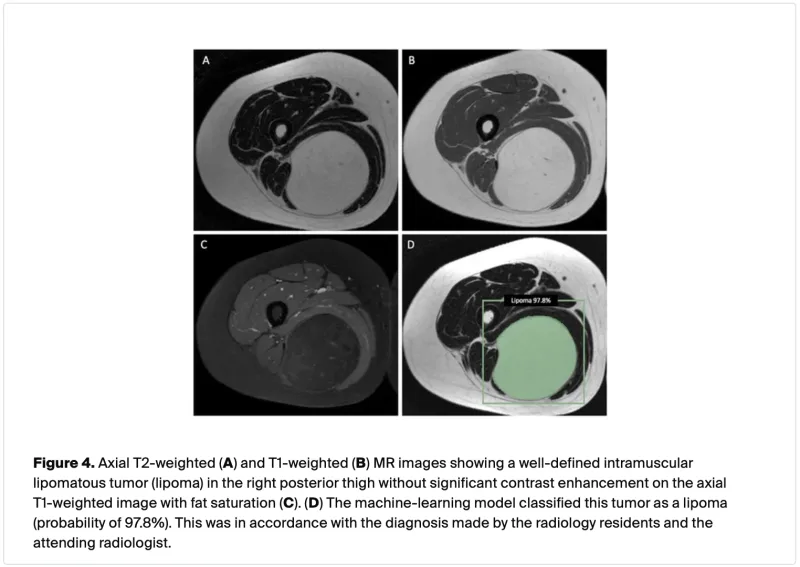

T2強調画像(A), T1強調画像(B)では, 内部は皮下脂肪と同様に, ほぼ均一に白い脂肪信号で, T1強調脂肪抑制像(C)では, 黒くなります.

引き続き, 15時過ぎから, 大腿部脂肪腫の中高年患者さんに対する摘出術を執刀.

腫瘍は, 20 cm近い大きさで, 大腿部後方のハムストリング筋の筋肉の間および筋肉の中に存在.

筋肉を分け入って, 腫瘍を傷つけないように丁寧に周りを剥がして, まるっと摘出しました.